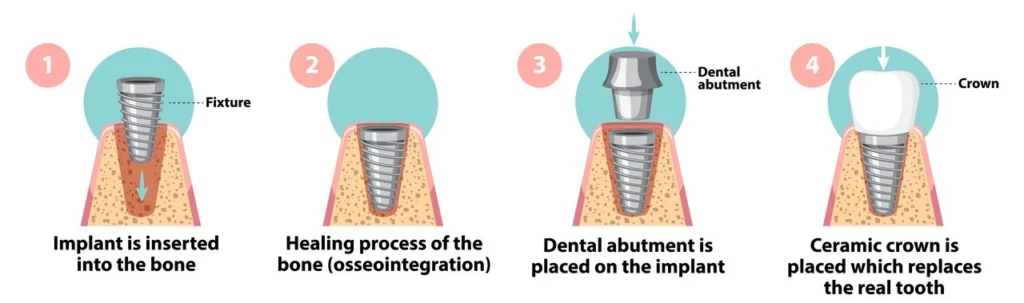

Dental implants are advanced prosthetic devices designed to replace missing teeth, offering both functionality and a natural appearance. Unlike traditional dentures or bridges, implants are anchored directly into your jawbone, mimicking the structure of natural tooth roots. Made from biocompatible titanium, dental implants fuse with the bone through a process called osseointegration, creating a stable foundation for replacement teeth such as crowns, bridges, or dentures.

Components of a Dental Implant: